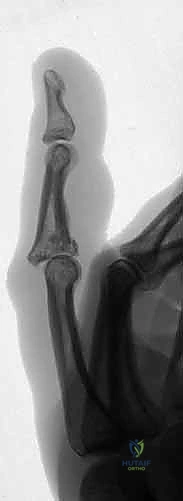

Figure 1A demonstrates a typical, more severe dorsal fracture-dislocation, involving approximately 65% of the volar articular surface.

Figures 1B and 1C illustrate proximal interphalangeal joint volar dislocations.

Figures 1D and 1E depict proximal interphalangeal joint pilon fractures.

The cornerstone of diagnosis is plain radiology. Crucially, we need true posteroanterior (PA) and lateral radiographs centered specifically on the injured PIP joint. Hand radiographs alone, often taken in the emergency department, are inadequate.

Figures 5A-C emphasize that hand radiographs are only interpretable with a true lateral view of the PIP joint.

Fluoroscopy is invaluable for assessing injury dynamics and joint stability in real-time. It helps differentiate stable from unstable injuries, whether fracture-subluxations, dislocations, or pilon fractures. Subluxation and dislocation are best visualized on the lateral radiograph and can be subtle, appearing as joint incongruity or the "triangle sign" (dorsal overhang of the middle phalanx base).

Figure 4E illustrates dorsal fracture-subluxation with joint incongruity and the classic V-sign.